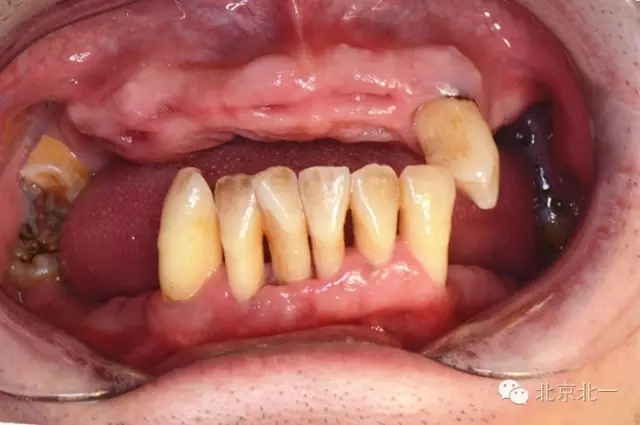

圖一:術(shù)前照片

重度牙周炎患者一例 牙齒無法保留